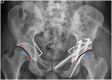

Poor prognosis factors in surgical treatment of acetabular fracture-dislocations have been well established but there is little information about how morphological abnormalities of the hip may affect the surgical outcome. Hip anatomy has a wide range of variations. Morphological abnormalities of the hip can also be observed in patients with acetabular fractures. We present a case of a complication in a patient with a complex acetabular fracture, acetabular retroversion and femoroacetabular impingement. A 31-year old male patient was transferred to our trauma center following a high speed road traffic accident. Trauma series CT revealed cerebral contusion, subdural hematoma, aortic dissection and a left transverse plus posterior wall acetabular fracture. The left hip was reduced and the acetabular fracture was treated with a Kocher Langenbeck approach in prone position. The pelvic X- ray evidenced an anatomic reduction and signs of acetabular retroversion with positive posterior wall sign and crossover sign. CT scan evidenced increased alpha angle in the femoral head neck junction. During the follow up, 2 months after the acetabular fixation, patient suffered a posterior left hip dislocation and a total cementless hip arthroplasty was performed. Patients with acetabular retroversion and femoroacetabular impingement (CAM lesion) may be at risk of posterior dislocation. The influence of acetabular version and impingement may be also closely involved in how challenging the determination of hip stability can be in patients with posterior wall acetabular fractures. Acetabular retroversion and FAI may be related to the dislocation of unstable patterns with small fragments (wall sizes less than 20%). In this case postoperative precautions were not enough. We believe capsular reattachment with anchors and bracing may be useful in these selected cases. As these patients are not candidates for retroPAO (the recommended treatment for acetabular retroversion) maybe arthroscopic anterior wall riming and CAM resection should be performed at an early stage to decrease or avoid fulcrum.